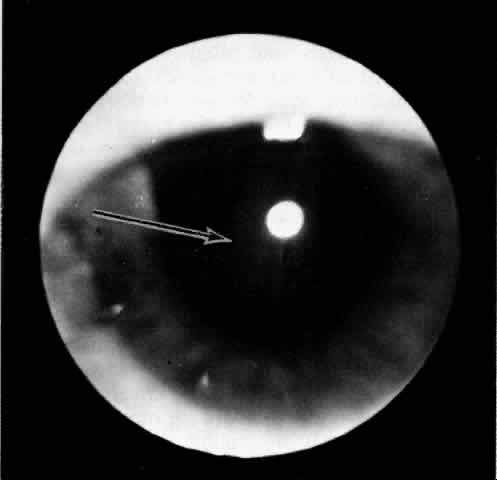

The presence of certain clinical characteristics may assist in the diagnosis of a ciliochoroidal effusion (Table 1). One clinical feature is choroidal edema. Choroidal edema may resemble a retinal detachment to a hasty observer; however, darkness of the uvea, lack of tremulousness, and normal retinal vessels indicate a probable uveal process (Fig. 1). The effusion may extend under the pars plana, allowing visualization of the ora serrata without scleral depression (Fig. 2).9 As shown in Figure 2, the surface of the elevation is convex and smooth, with a solid appearance and a homogeneous grayish color. A shallow anterior chamber and a low intraocular pressure may also suggest the diagnosis. Myopia in the presence of anterior displacement of the lens-iris diaphragm may be another diagnostic clue.10,11

Fig. 2. The ora serrata is visible in the pupillary space due to a ciliochoroidal effusion that developed after retinal detachment surgery in an aphakic eye. The arrow indicates the ora bay. (Courtesy of Retina Service, Wills Eye Hospital, Philadelphia)